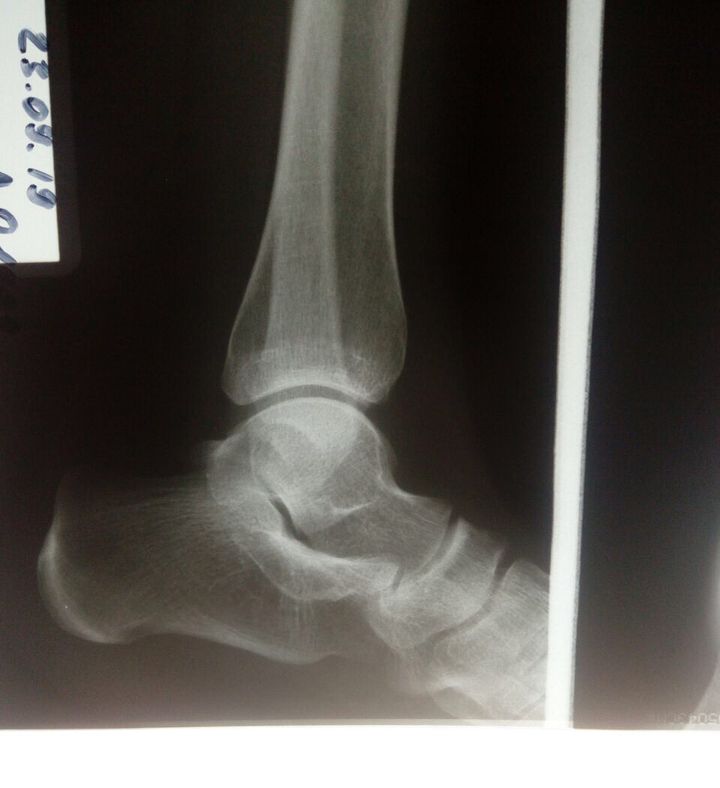

I think In the lower most portion of tibia, anteriorly, in front of fibular shadow, there's some thing, like a dark area. Or maybe a normal x-ray?

It’s not a normal as her foot feels like it’s going to fall… So I fail to make a correct diagnosis owing either to she sent me x-ray only

Maybe some nerve injury that made her lose joint position sense?